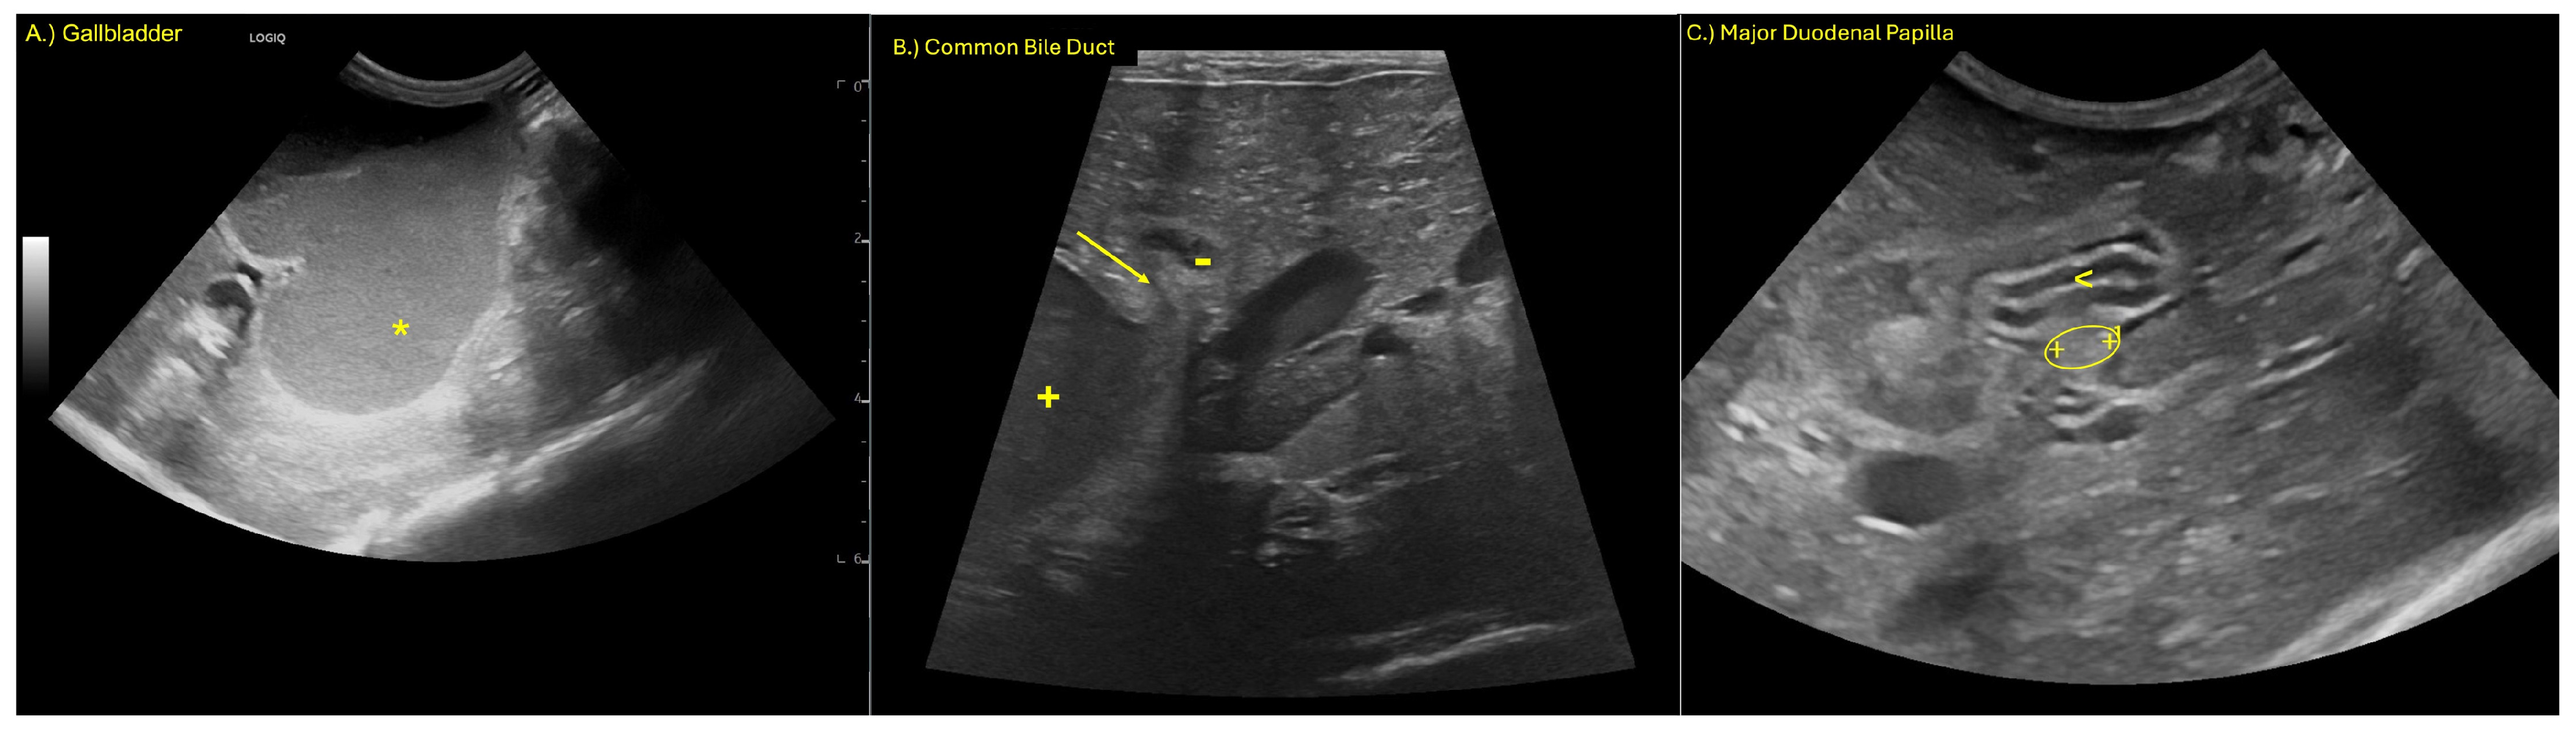

Ultrasonographic evaluation revealed marked dilation of the gallbladder and CBD (Figure 1). Both contained a marked amount of gravity-dependent echoic material with hyperechoic foci and speckles, alongside non-gravity-dependent anechoic material. The walls of the gallbladder and CBD were moderately thickened and hyperechoic, and they exhibited mild irregularity.

The CBD demonstrated abrupt luminal tapering proximal to the major duodenal papilla (Figure 1B), while the papilla itself appeared within normal limits sonographically. Moderate dilation of the intrahepatic bile ducts was noted. The pancreatic duct was mildly dilated at its most distal aspect (Figure 1B). The stomach was moderately displaced toward the right cranial abdomen, consistent with mass effect from the adjacent biliary structures. A mild amount of anechoic peritoneal effusion was identified.

The findings were consistent with an extrahepatic biliary obstruction, most likely at or just proximal to the major duodenal papilla, secondary to a mucous plug, stricture, or other causes of obstruction. Reactive peritoneal effusion and mild pancreatic ductal dilation may reflect early secondary inflammatory or pressure-related changes.

Figure 1. (A) Marked dilation of the gallbladder (*), (B) marked dilation of the CBD (+) with luminal tapering (arrow) and mild distension of the pancreatic duct (-), and (C) major duodenal papilla (oval) entering the duodenum (<).